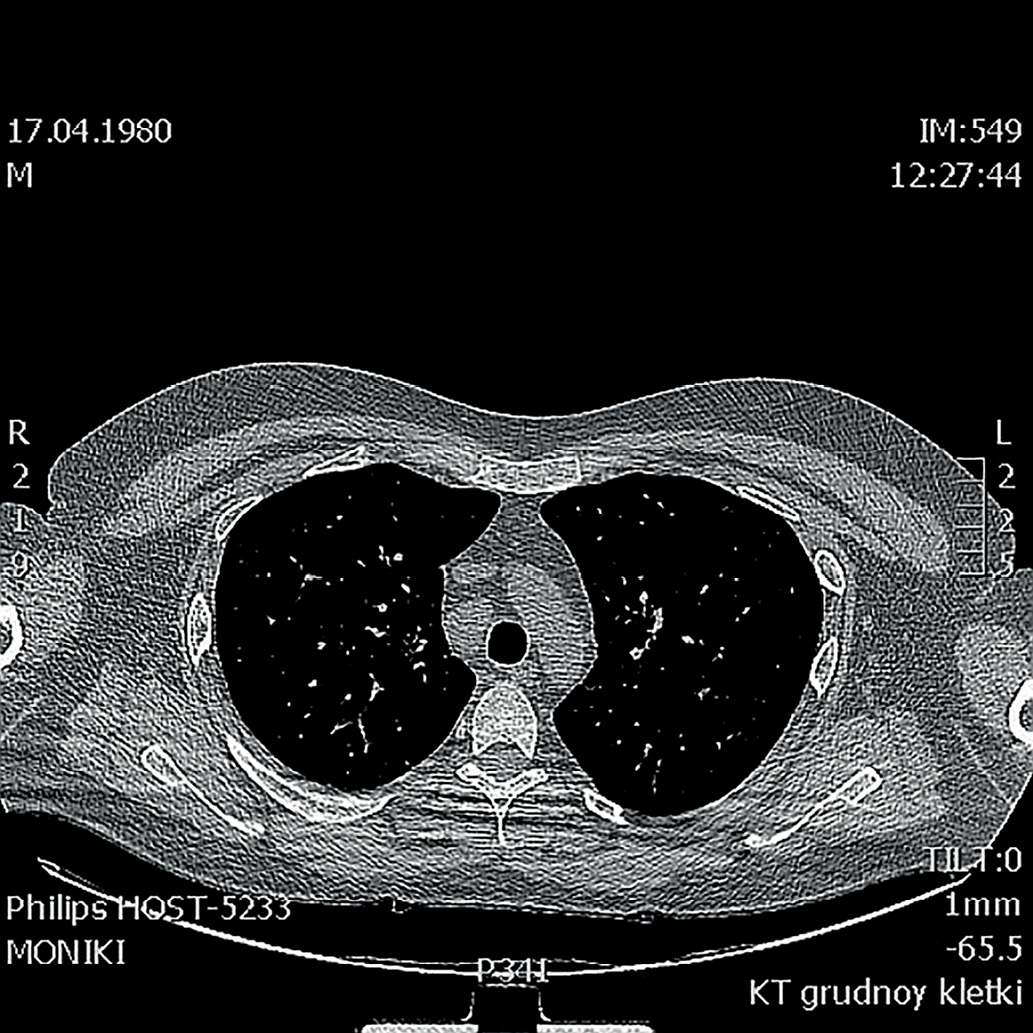

Рисунок 3. КТ органов грудной клетки от 2018г.

(Немногочисленные мелкоочаговые тени лимфогенного распределения, лучше визуализируются в проекции междолевой плевры правого легкого).

Figure 3. CT scan of the chest from 2018

(A few small focal shadows of the lymphogenous distribution are better visualized in the projection of the interlobar pleura of the right lung).